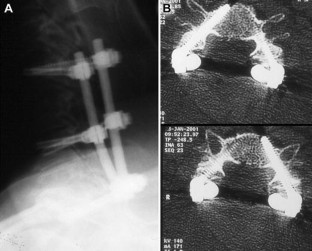

Fig. 2